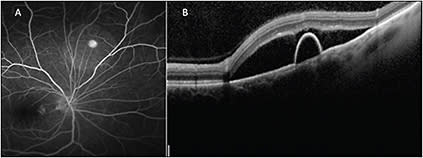

The availability of widefield OCT may have allowed for imaging of the PED and optic nerve within the same scan. Targeted OCT allows for improved assessment of stability or progression of the extent of subretinal fluid at follow-up (Figure 2, page 39).

Figure 2. Fluorescein angiography (A) shows a pinpoint area of hyperfluorescence consistent with the diagnosis of CSR. A peripheral targeted SD-OCT B-scan (B) shows both subretinal fluid and a pigment epithelial detachment in a patient with peripheral CSR.